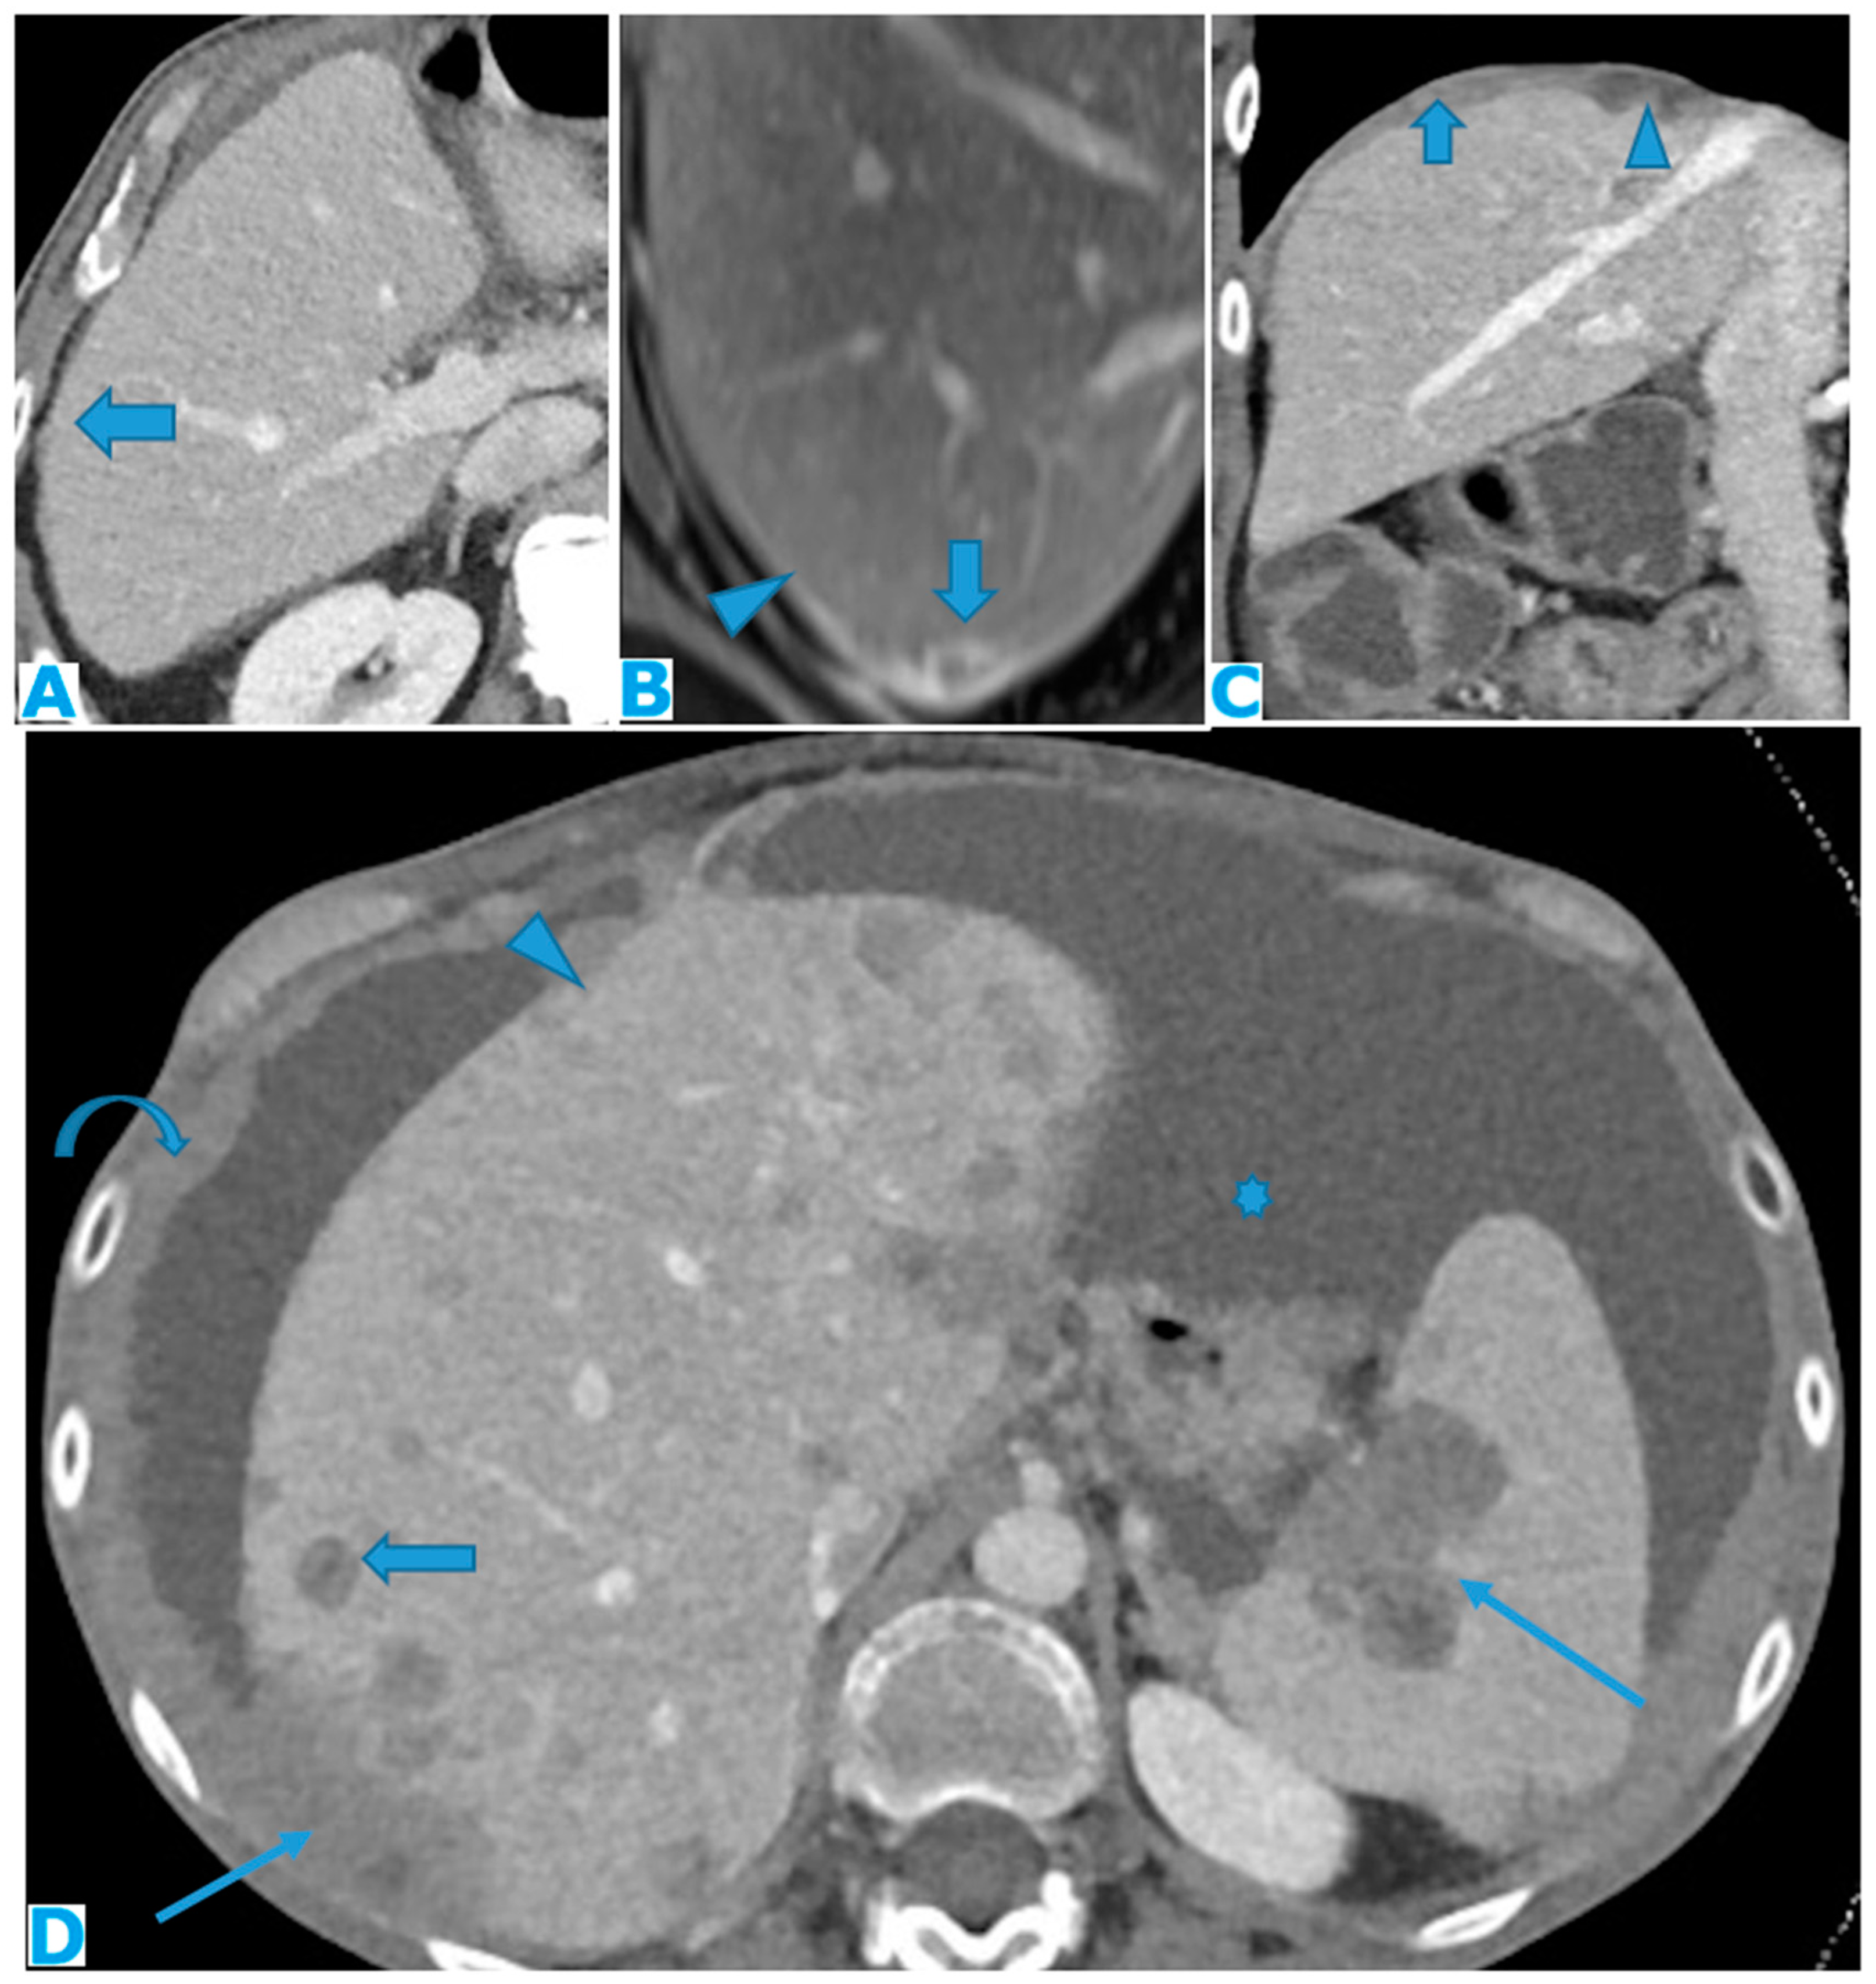

Figure 9.

Axial CE-CT (A): PC from colon carcinoma: Note the subtle irregularities of the liver contour caused by the deposit seeding within the peritoneum covering the hepatic surface. CE portal phase FST1WI (B): PC from cervical carcinoma: Notice the difference between the linear subcapsular deposits (arrowhead) and the biconvex subcapsular deposit with parenchymal invasion (arrow): observe the scalloped appearance of the underlying parenchyma. CE-CT coronal MPR (C): PC from colon carcinoma: Thickening of the right diaphragm caused by deposit seeding (arrow). Notice the difference with the subcapsular deposits that scallop the liver contour (arrowhead). Axial CE-CT (D): PC from ovarian carcinoma: Subcapsular deposits with parenchymal invasion (thin arrows), both hepatic and splenic. Observe how they differ from hepatic metastases, well defined and completely surrounded by parenchyma (arrow). Note also perihepatic (arrowhead) and right subphrenic deposits (curved arrow). Ascites (*).